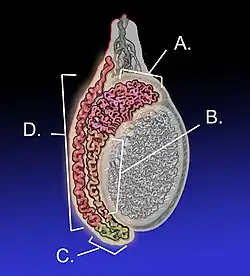

Epididymitis is a medical condition characterized by inflammation of the epididymis, a curved structure at the back of the testicle.[1] Onset of pain is typically over a day or two.[1] The pain may improve with raising the testicle.[1] Other symptoms may include swelling of the testicle, burning with urination, or frequent urination.[1] Inflammation of the testicle is commonly also present.[1]

Epididymitis usually has a gradual onset. Typical findings are redness, warmth, and swelling of the scrotum, with tenderness behind the testicle, away from the middle (this is the normal position of the epididymis relative to the testicle). The cremasteric reflex (elevation of the testicle in response to stroking the upper inner thigh) remains normal.[1] This is a useful sign to distinguish it from testicular torsion. If there is pain relieved by elevation of the testicle, this is called Prehn's sign, which is, however, non-specific and is not useful for diagnosis.[13] Before the advent of sophisticated medical imaging techniques, surgical exploration was the standard of care. Today, Doppler ultrasound is a common test: it can demonstrate areas of blood flow and can distinguish clearly between epididymitis and torsion. However, as torsion and other sources of testicular pain can often be determined by palpation alone, some studies have suggested that the only real benefit of an ultrasound is to assure the person that they do not have testicular cancer.[14]: p.237 Nuclear testicular blood flow testing is rarely used.